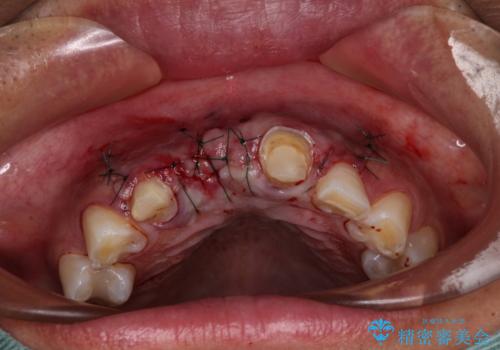

抜歯をすると歯肉が窪んでしまうので、傷口の治りを待って、歯肉移植を行うこととしました。

歯肉移植や根管治療終了後、オールセラミッククラウンおよびブリッジにて補綴することとしました。